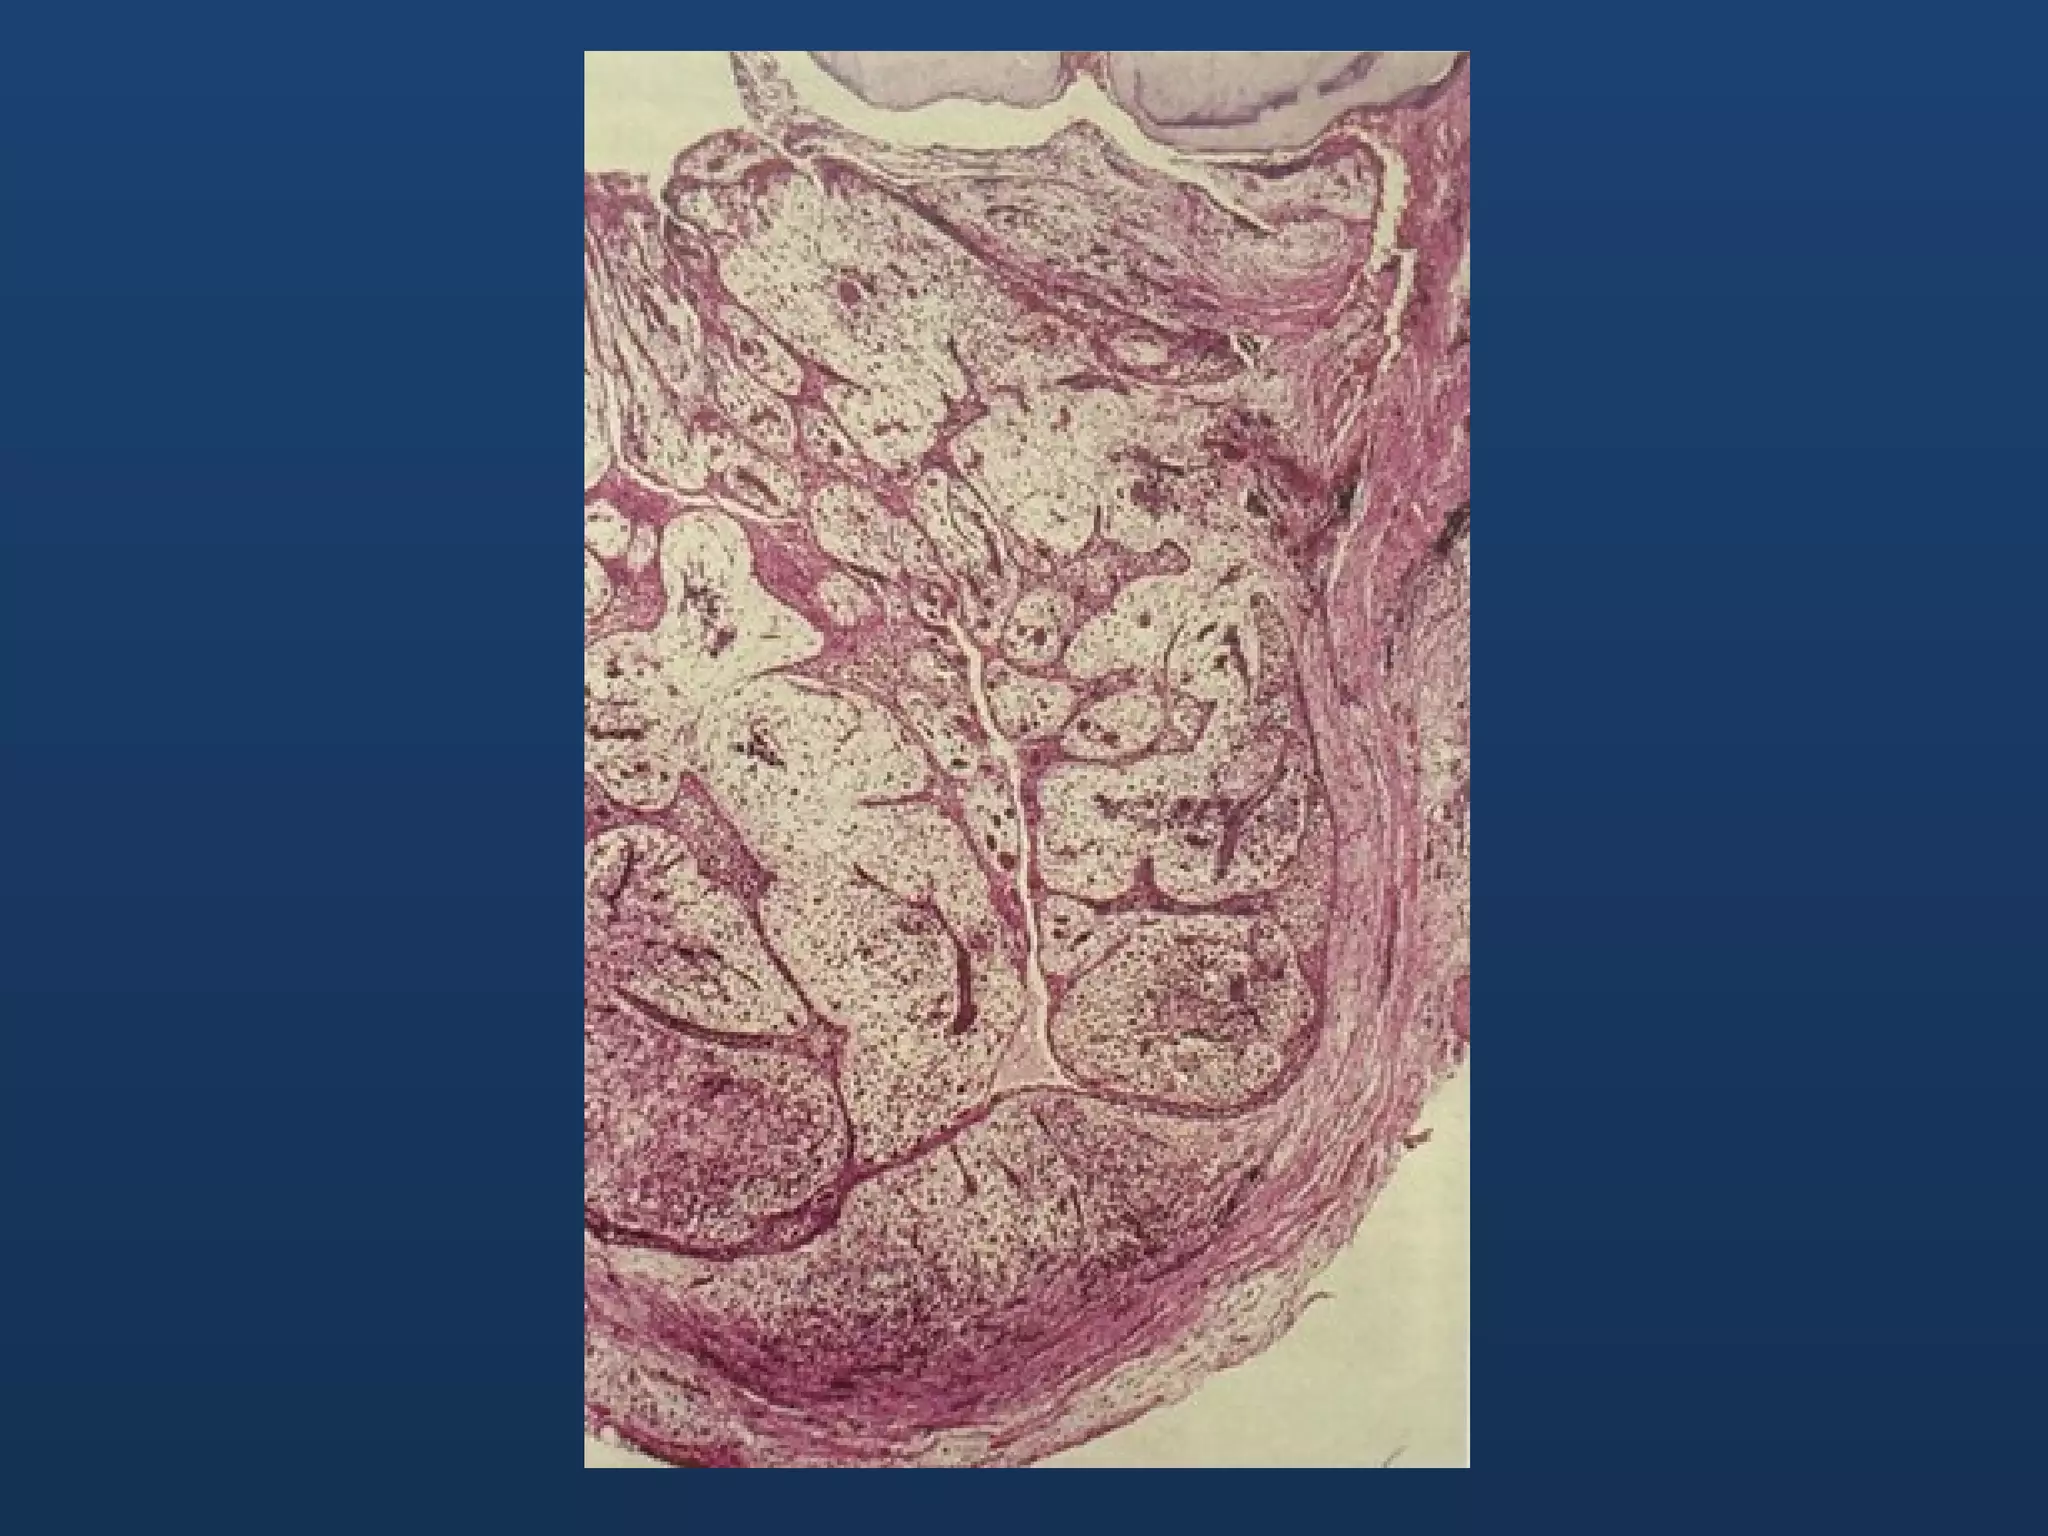

Histopathology • Lining isa thin, regular, 2-5 cells thick, non- keratinized, stratified squamous or cuboidal • Fibrous CT capsule free from inflammatory cell infiltration • Occasional cholesterol clefts

• #26 This is a section showing an eruption cyst just below the mucosa We can see the Fibrous connective tissue capsule free from inflammatory cell infiltration